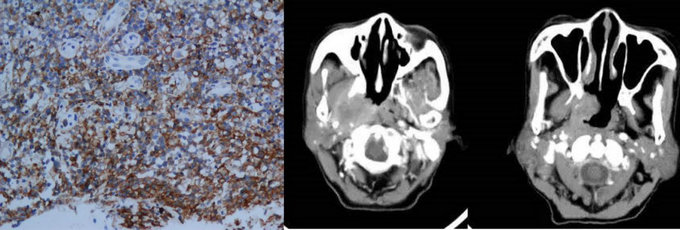

½áÍâ±ÇÐÍNK/Tϸ°ûÁܰÍÁö£¨¼ò³ÆNK/TÁܰÍÁö£©ÊÇÎÒ¹úµÚ¶þ³£¼ûµÄ·Ç»ôÆæ½ðÁܰÍÁöÑÇÐÍ£¬£¬ÔÚÎ÷Å·¹ú¼ÒÓÐÊý£¬£¬ÌØ·¢ÓÚÖйúµÈÑÇÖÞ¹ú¼Ò¡£¸Ã²¡¹Å°åÖÎÁÆÐ§¹ûÇ·¼Ñ£¬£¬Ô¤ºó²»¼Ñ¡£½áÍâ±ÇÐÍNK/Tϸ°ûÁܰÍÁöûÓÐ×ÔÁ¦·ÖÆÚϵͳ£¬£¬ºã¾Ã½èÓûôÆæ½ðÁܰÍÁöAnn Arbor·ÖÆÚ¡£

NK/TÁܰÍÁö²¡Àí¼°Ó°ÏñÌåÏÖ

¿ÉÊÇÒÀ¾ÝAnn Arbor·ÖÆÚ£¬£¬Ô¼80%²¡ÀýΪ¾ÖÏÞÆÚ£¬£¬¶øÕⲿ·Ö¾ÖÏÞÆÚ»¼ÕßµÄÖÎÁÆÐ§¹ûºÜ²î£¬£¬Ô¤ºó²»Á¼£¬£¬ËµÃ÷Ann Arbor·ÖÆÚÄÑÒÔ׼ȷ·´Ó³½áÍâ±ÇÐÍNK/Tϸ°ûÁܰÍÁöµÄÇÖÕ¼³Ì¶È£¬£¬¹ØÓÚÖÎÁÆ·½°¸µÄÑ¡ÔñºÍÔ¤ºóÅж¨¼ÛÖµÓÐÏÞ¡£Ö×ÁöµÄ¾«×¼·ÖÆÚÊÇ¿ªÕ¹ºÏÀíÖÎÁƵĻù´¡£¬£¬Ñ°ÕÒ¸üΪ׼ȷÓÐÓÃµÄ·ÖÆÚϵͳ£¬£¬³ÉΪÁËÏÖÔÚÕë¶ÔNK/Tϸ°ûÁܰÍÁö¾ÙÐо«×¼ÖÎÁƵÄÒªº¦Ìõ¼þÖ®Ò»¡£